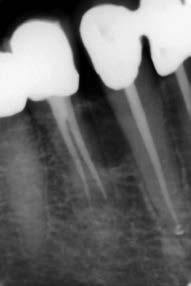

The canal was sealed with a Thermafil™ cone (Dentsply Sirona) with an apical diameter of 0.30 mm (Figs. 3-4).

glass fibre Figure 3: Root canal therapy completed under proper isolation. Figure 4: Radiography of completed root canal therapy and reconstruction made completely in glass hybrid cement. Figure 5: Clinical crown lengthening with a minimally invasive technique without mesial and distal discharges. Note the proximity of the reconstruction in glass hybrid material to the mesial bone ridge. Figure 6: Suture at the end of surgical therapy. It was left in place for 7 days Figure 7: Suture removal at 7 days. Post-surgical edema is still present.